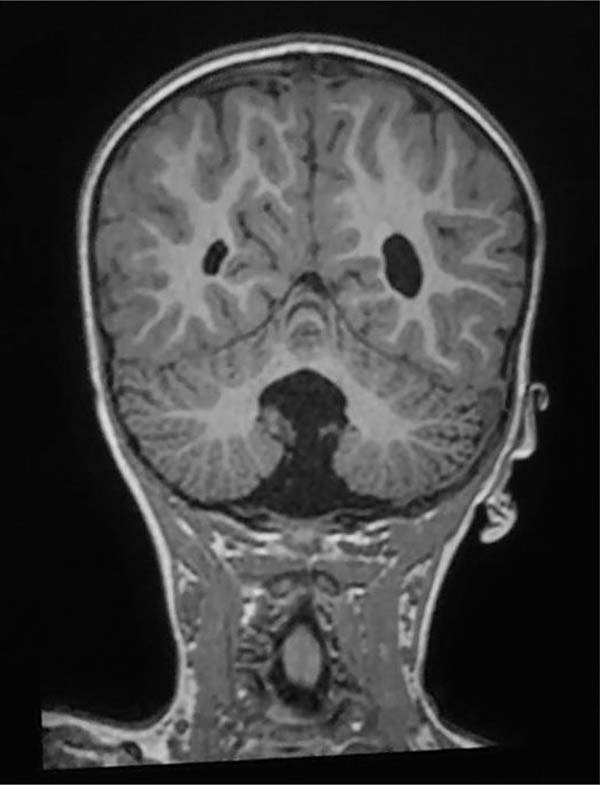

A RM do crânio revelou hipoplasia do vérmis cerebelar, dilatação do quarto ventrículo e comunicação com a cisterna magna sem sinais de hidrocefalia. (►Fig. 2) Não foram observadas alterações esqueléticas ou renais.